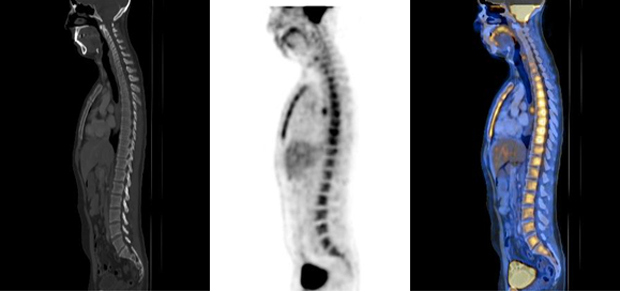

Puede existir actividad médula ósea reaccional a tratamientos estimulantes de colonias granulocíticas, post quimioterapia y/o por anemias severas (fig.3).